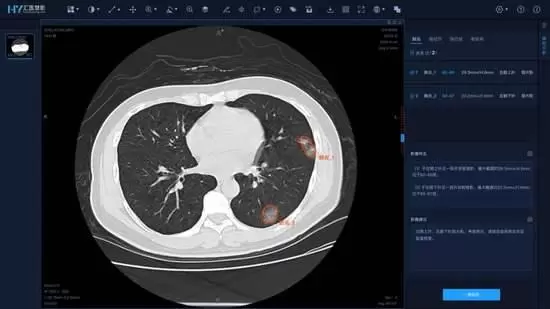

华为IdeaHub瞄准互联网诊疗领域,可以同时为患者端、多地会诊医生及医疗机构输出4K医疗影像数据,能够让多学科会诊医生实时通过影像病理信息进行讨论,给出综合诊断及意见,为智慧医疗带来一次升级。

这时候,华为IdeaHub价值体现出来,通过投屏码投屏、二维码投屏等方式,科室医生之间可以快速共享像病人CT、诊断报告等文件,而不同园区的医疗人员,可以同时在企业智慧屏上书写、标注,纵向上,这方便了上下级专家与主治医生共同制定诊疗方案,横向上,这可以让多科室专家的疑难杂症更便利。

而华为IdeaHub云会议视频可达到1080p云会议,共享文档拥有4K超清分辨率,色域编解码能实现BT.2020标准。例如在郑大一附院的应用中,借助华为IdeaHub能够让医护人员清晰看到远端病人的医疗图像数据,应对影像会诊等专业诊疗情况,同时,华为IdeaHub也能支撑一些需要高清晰、高还原图像辅助的高难度手术需求,在智慧医疗解决方案中实现更清晰化的展示助力。